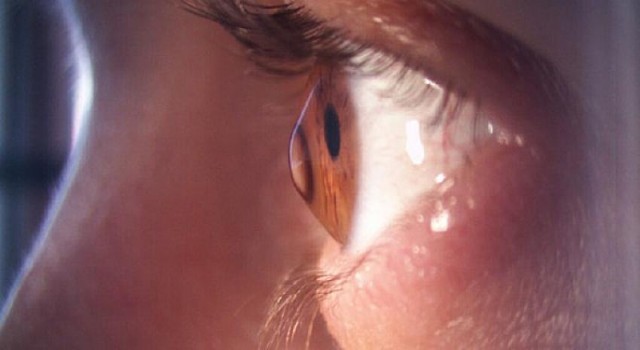

Keratokunus, kornea adı verilen ve gözün en önündeki saat camı gibi olan saydam kırıcı tabakanın ilerleyici bir şekilde incelerek öne doğru kronik tarzda uzamasıdır. Kadınlarda daha sık görülen keratononus, korneanın kırma gücünü değiştirerek orta veya ağır derecede düzensiz astigmata ve bulanık görmeye sebep olur. Keratokonus hastalığının son evresinde korneada şişme ve beyazlaşma görülebilir. Keratokonusun kelime anlamı da koni şeklinde kornea demektir. Halk arasında gözde incelme, gözde kornea incelmesi olarak da bilinir. Korneanın şekli bozulunca görme bozulur.

İlk belirtiler görmede çarpıklık ve bulanıklıktır. Belirtiler genellikle 15-25 yaşlar arasında çıksa da daha erken veya daha geç de görülebilir. Bu dönemde genellikle miyop astigmat tanısıyla gözlük verilir. Ancak Orbscan ve Pentacam adı verilen kornea topografi yöntemi ile çok erken dönemde dahi saptanabilir. Hastalık ilerledikçe korneadaki şekil değişikliği artar ve görme bozukluğu daha belirginleşir.